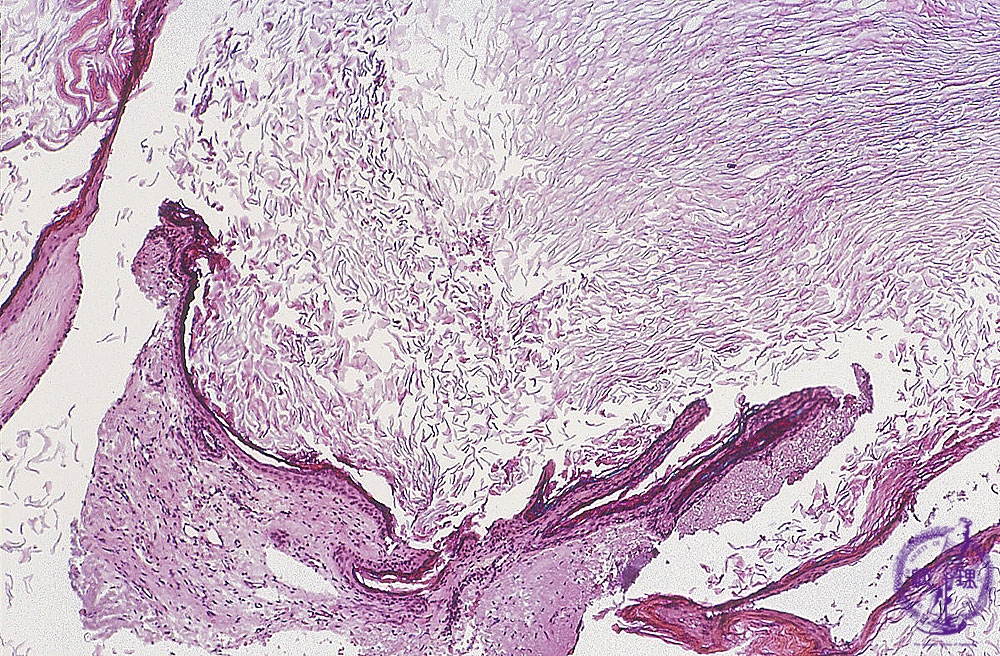

Fragments of keratinizing stratified squamous epithelium are characteristic of cholesteatomas.